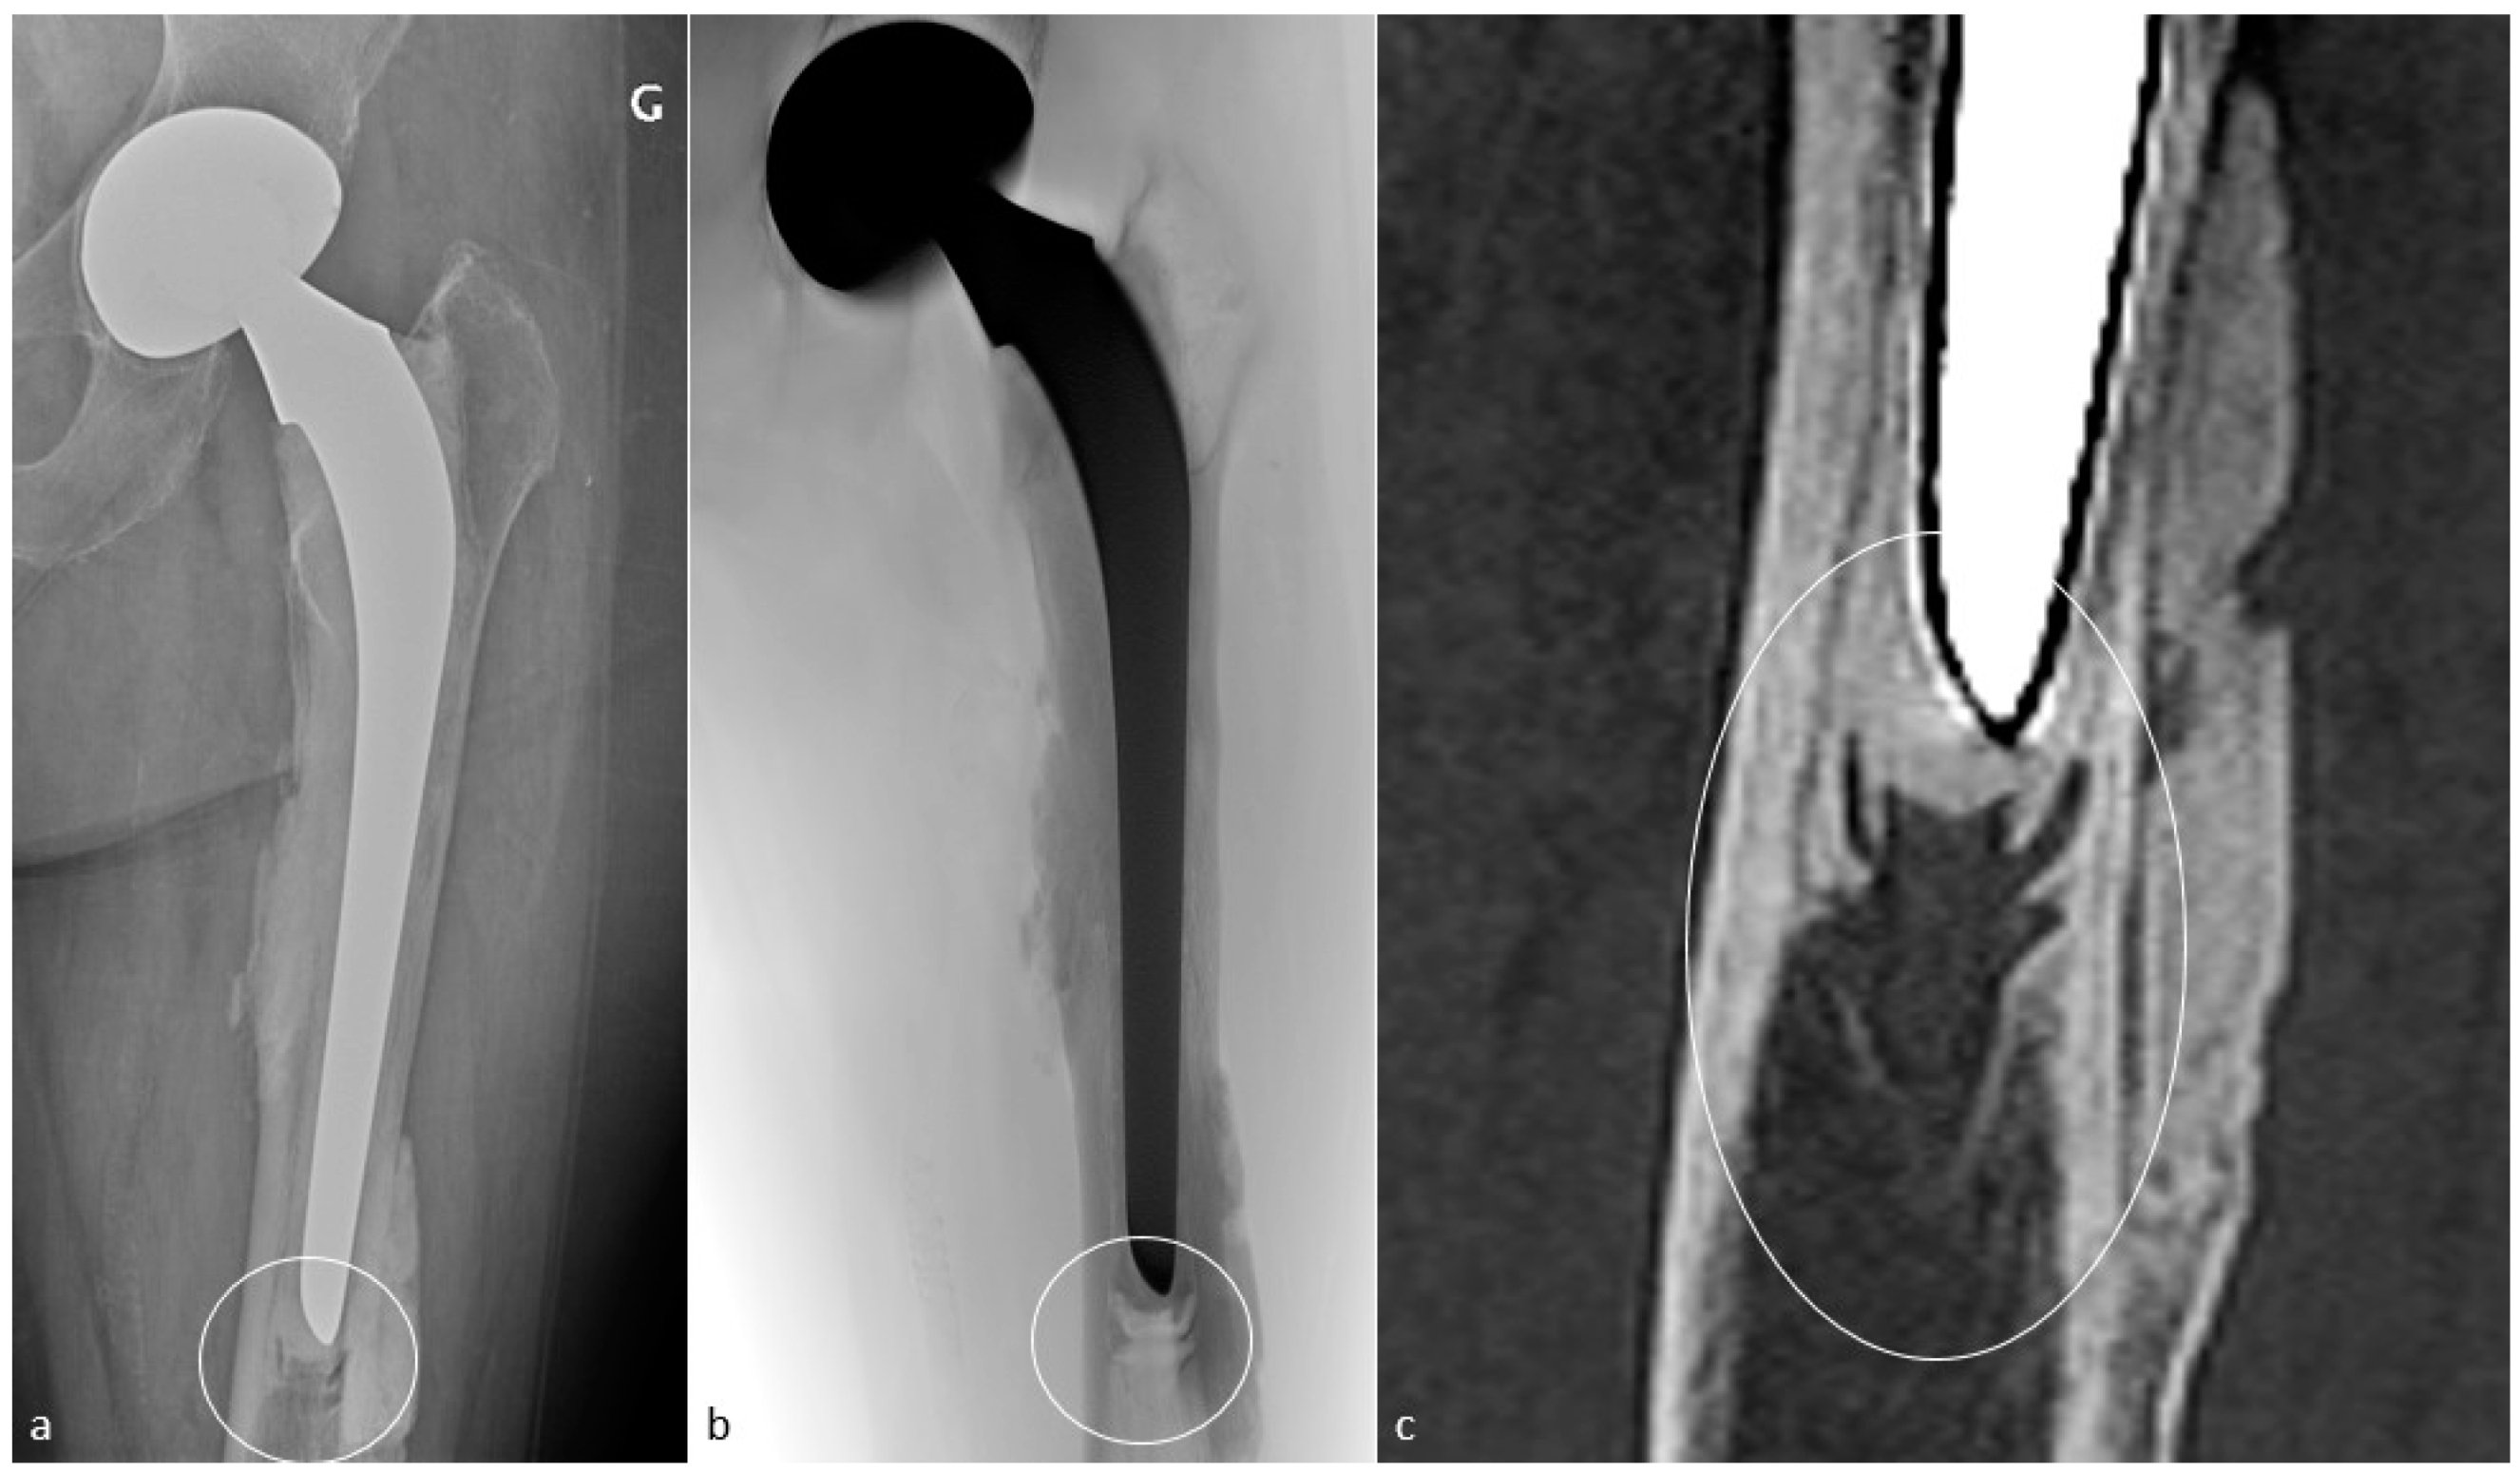

4.10. Peri-Prosthetic Fractures and Stress Reactions

4.10.2. Imaging